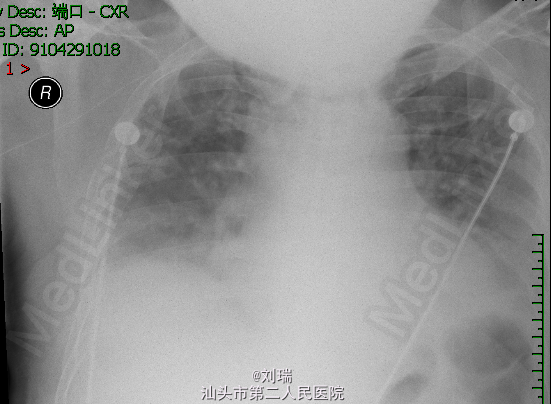

查体:急性面容,血压:110/90mmHg,心率116次/分,皮氧:99%,双肺可闻及少许哮鸣音;腹部膨隆;双下肢浮肿。患者D-二聚体由入院时470ug/L升至1090ug/L;床边胸片(图2)对比入院时(图1):见心影增大。